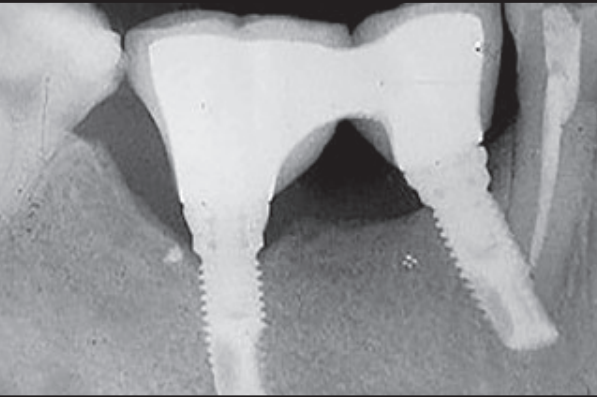

尽管下颌神经上方骨高度充足(图1a),但因张口受限及术野暴露困难,仅能植入短种植体(10 mm);

备洞时钻针远中向倾斜过度,导致第一前磨牙根尖区牙髓神经断裂(图1b)。

(b) 术后X线片表现

术后影像证实:

两枚种植体就位良好,骨结合界面清晰;

第一前磨牙根尖区可见神经横断征象,系备洞时钻针远中向偏移所致。

注意下颌右侧第一前磨牙的根尖神经横断。(a) 横断面图像。(b) 3D立体图。